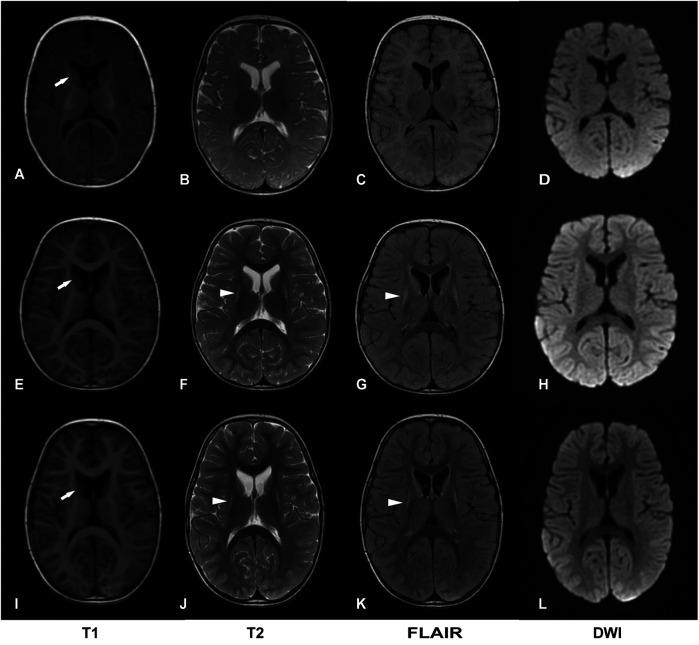

We report a third case of Leigh syndrome associated with variants in a 2-year-old boy. The patient exhibited with global developmental delay, dystonia, early-onset chorea, and elevated serum lactate levels. Follow-up brain magnetic resonance imaging at 2 years revealed progressive degenerative lesions in the bilateral basal ganglia. Muscle biopsy showed abnormal mitochondrial accumulation beneath the sarcolemma, and the oxygen consumption rate was reduced in skin fibroblasts. Whole-exome sequencing identified two novel compound heterozygous variants: c.42+1G>A (p.?) and c.296G>C (p.Arg99Pro).

我们报告了一名2岁男孩中与该变异相关的Leigh综合征的第三例病例。该患者表现为全面发育迟缓、肌张力障碍、早发性舞蹈症和血清乳酸水平升高。2岁时的随访脑磁共振成像显示双侧基底神经节有进行性退行性病变。肌肉活检显示肌膜下线粒体异常积聚,皮肤成纤维细胞的氧消耗率降低。全外显子组测序鉴定出两个新的复合杂合变异:c.42+1G>A(p.?)和c.296G>C(p.Arg99Pro)。